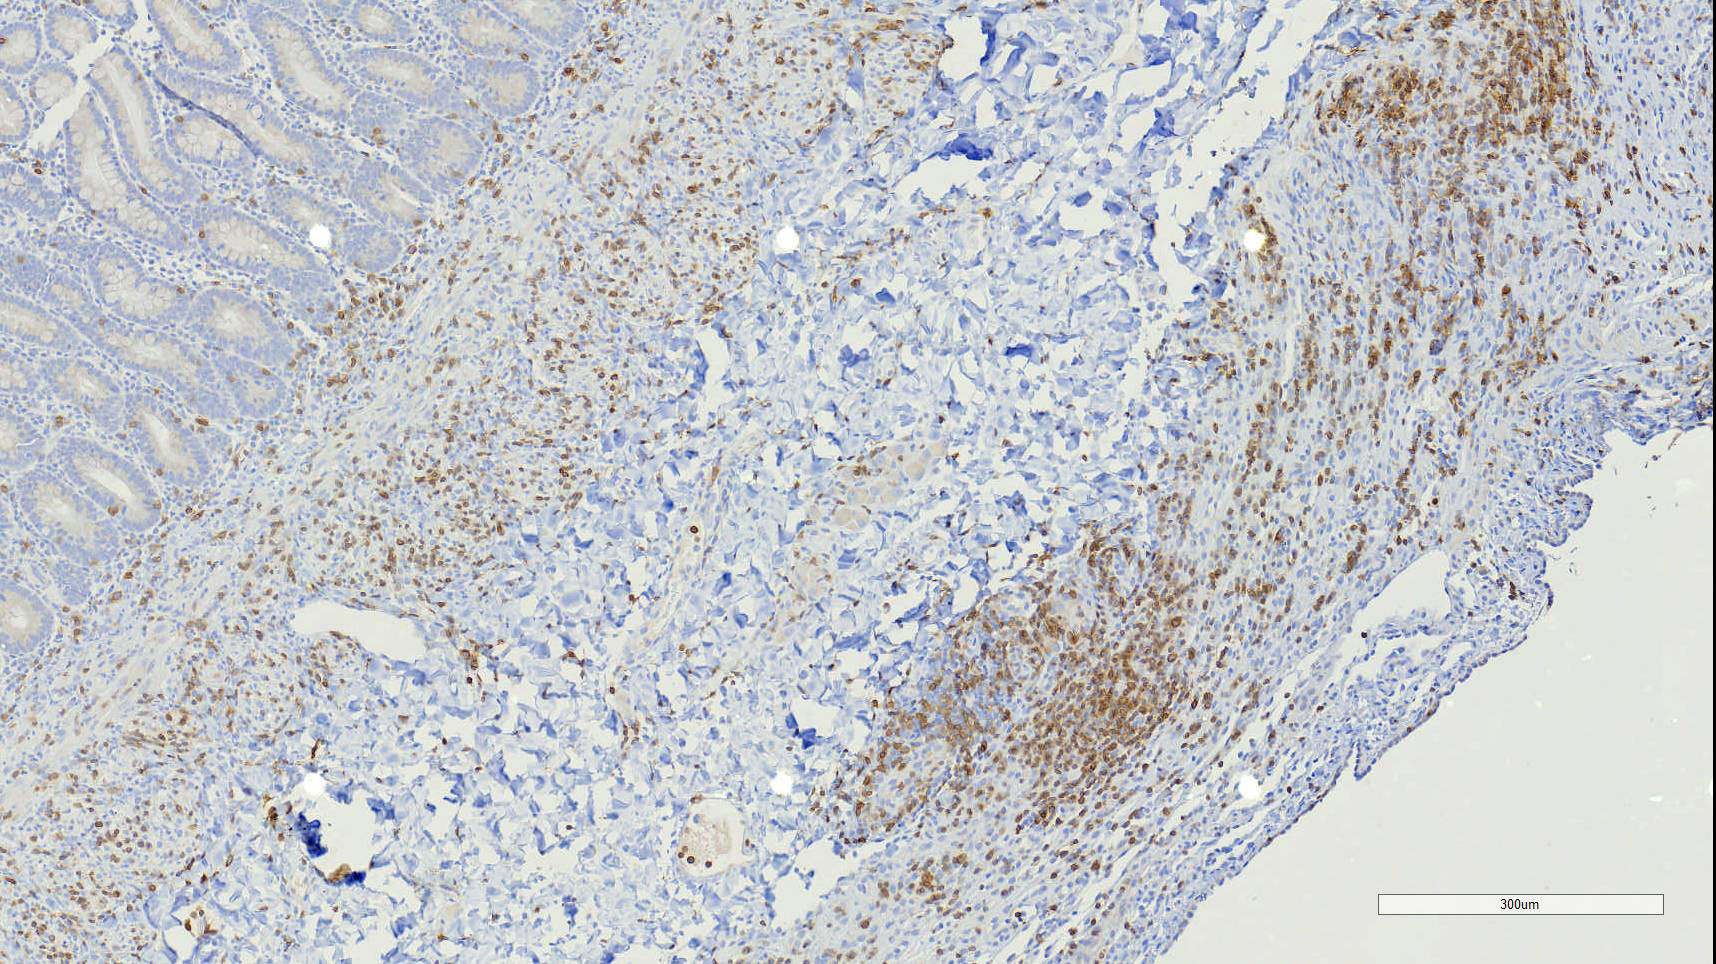

Duodenum, jejunum and ileum: Diffusely throughout the sections, there is partial to complete loss of the leiomyocytes of the outer and inner muscularis, which are multifocally replaced by loose fibrous connective tissue (fibrosis). The remaining smooth muscle is infiltrated by large numbers small and intermediate lymphocytes, few macrophages and neutrophils. The same inflammatory infiltrate is present throughout the muscularis mucosae. Remaining leiomyocytes have pale, frequently vacuolated cytoplasm. In the submucosa, muscularis and serosa there are small to moderate numbers of perivascular lymphocytes. Small lymphocytes, and infrequently neutrophils, surround or infiltrate the myenteric and submucosal ganglia, though neurons do not exhibit degenerative changes. The lamina propria contains a markedly increased number of lymphocytes, plasma cells and a mildly increased number of eosinophils. The epithelium is diffusely overlain by myriad bacterial rods. The serosa is mildly expanded by increased clear space (edema) and is lined multifocally by markedly hypertophied mesothelium. In the stomach a similar process is observed but restricted to the outer aspect of the muscularis with a patchy/multifocal distribution and sparing of the muscularis mucosae. (section not submitted).

Duodenum, jejunum and ileum: Severe, diffuse, chronic lymphocytic leiomyositis with severe muscularis atrophy; marked, diffuse, chronic lymphoplasmacytic enteritis.

Microscopic findings reported for this condition consist of mild to marked mononuclear infiltrate, myofiber degeneration and fibroplasia or fibrosis centered within the muscularis propria of the stomach, small and large intestinal wall with the jejunum being the most severely and chronically affected segment.7,15 In early lesions the inflammation and smooth muscle degeneration are segmental, random between the outer and inner muscularis layers and sparing of the muscularis mucosae.15 Concurrent cecal involvement leading to impaction has also been described.5 Consistent histologic findings included T-lymphocyte inflammation within the muscularis propria with relative sparing of the mucosa, submucosa and neural plexuses.14 In one case report the inflammatory infiltrate was predominantly of B-lymphocytes and featured extensive angiogenesis.6 Leiomyocytes appear to be the target of the inflammation given the presence of various stages of degeneration leading to complete myofiber loss in chronic stages of the disease. Superficial inflammation is a frequent secondary finding in CIPO and has been associated with bacterial overgrowth, which were changes observed in this case.6 Neuropathy has not been a feature in most reports of canine CIPO. Inflammatory cells obscuring the myenteric and submucosal plexuses in this case were considered an extension from the neighboring inflammation as no degenerative changes were observed in the neurons. Myenteric ganglionitis has, however, been reported occurring concurrently with leiomyositis.10

Small intestine: Leiomyositis, lymphocytic, chronic, diffuse, severe, with marked smooth muscle loss and fibrosis.